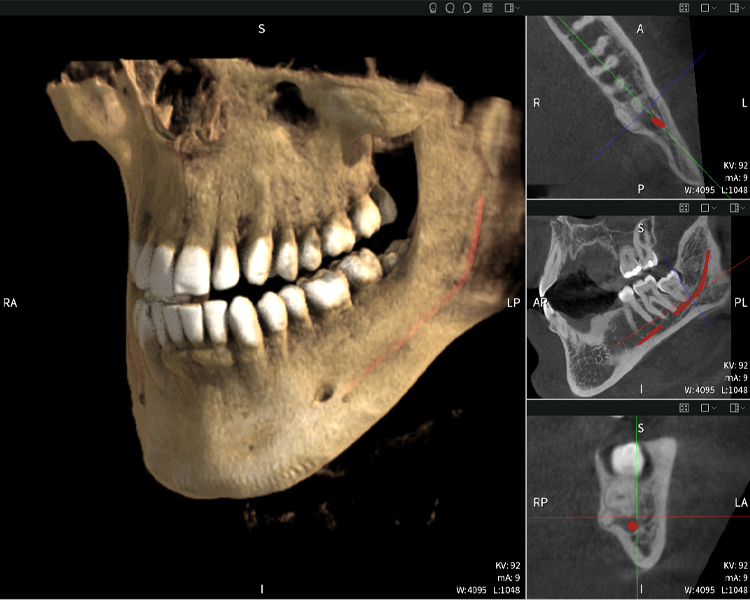

Figures b–d show various views of a 3D reconstruction of the mandible, providing a comprehensive overview of the mandibular anatomy, the position of the nerves in relation to the teeth, and allowing assessment of tooth symmetry and alignment.